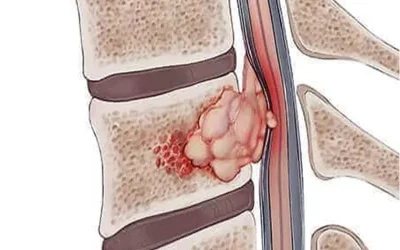

تومور استخوانی کوردوما

تومور استخوانی کوردوما یکی از انواع نادر و پیچیده تومورهای استخوانی است که به طور معمول در نواحی انتهایی ستون فقرات و جمجمه، به ویژه در نواحی نزدیک به مهرههای استخوانی و نواحی باسن، ایجاد میشود....